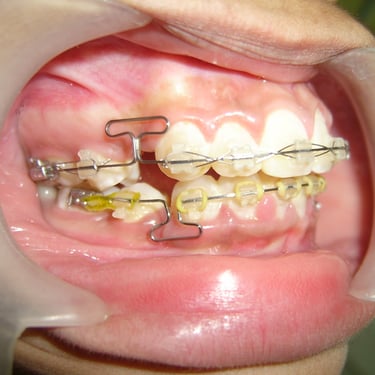

Orthodontics & Dentofacial Orthopaedics

Fix metal braces Self ligating braces Ceramic braces Colored braces Aligners/Invisalign Lingual braces TMJ disorders Cleft lip and palate patients Head gear Face mask Chin cup Ortho mini implants/TAD Essix retainer Fix lingual retainer Functional appliances Twin block appliance Removable ortho